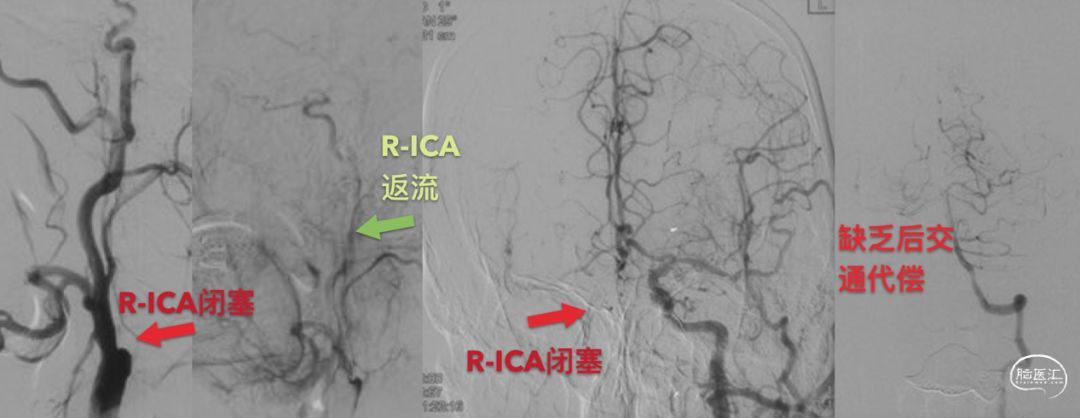

患者还在当地进行了造影,提示右侧ICA闭塞,眼动脉代偿,返流到ICA的岩骨段;另有前交通代偿,但似乎代偿比较差。

造影证实了外院的诊断,右侧ICA闭塞,有较长的返流血流,应该是可以再通的。

手术以复合手术的方式开始,常规暴露颈动脉,沿长轴剪开颈动脉。在ICA闭塞处溢出少量粘稠的黑色液体,这是尚未形成固体形态的血栓。